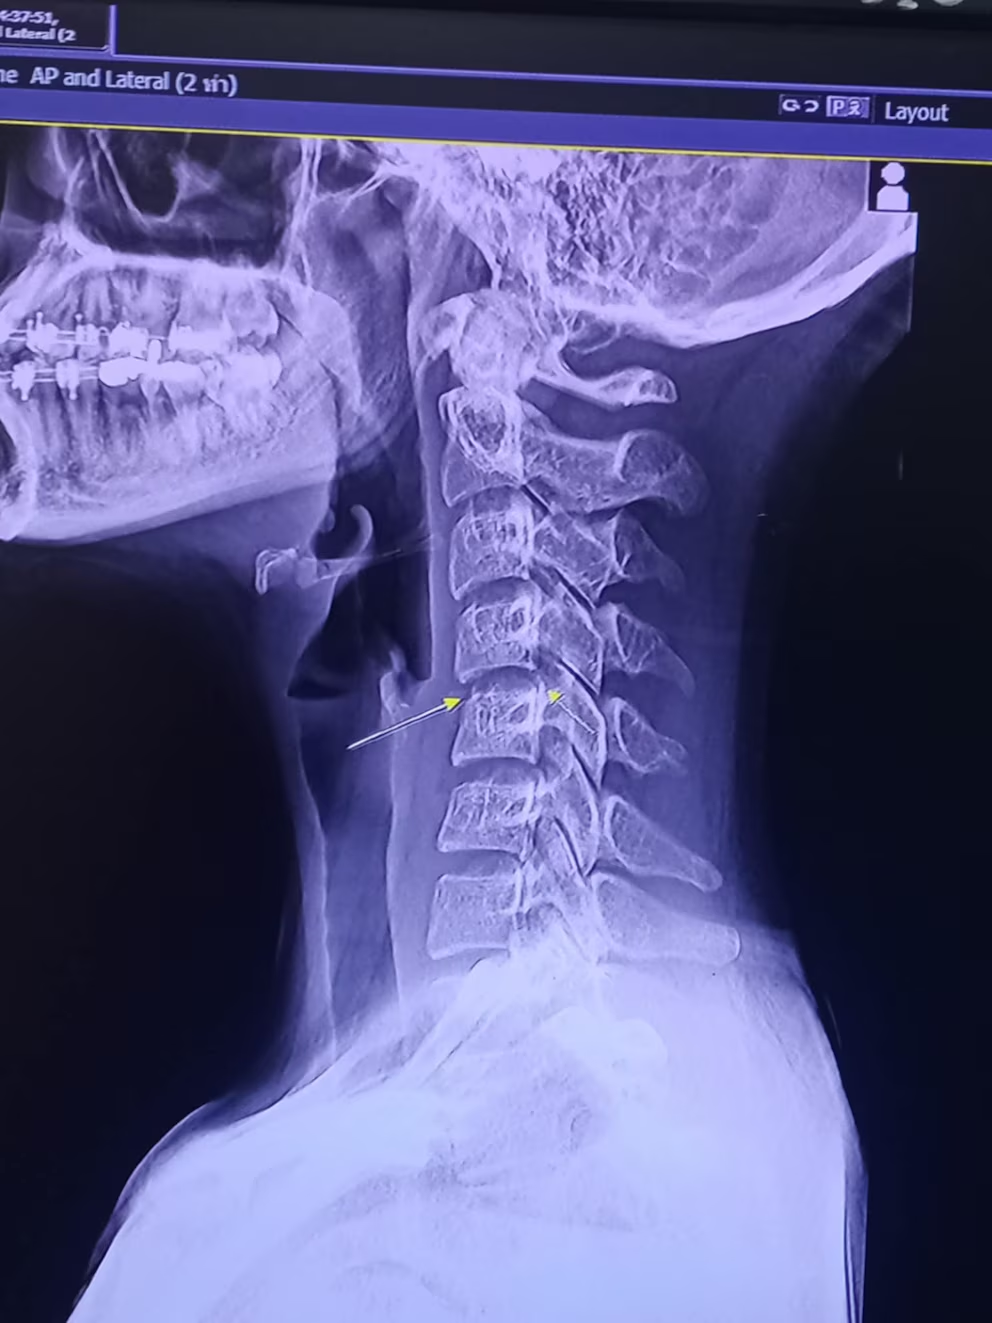

“En el país hay una Asociación Argentina de Masajistas, que otorga títulos y enseña que el trabajo de la manipulación cervical y la manipulación lumbar tiene que estar hecha por especialistas y siempre con un registro previo de estudios por imágenes para evaluar si el paciente tiene, por ejemplo, algún problema arterial en el cuello o un canal cervical estrecho, que puede ser el motivo de producir una lesión grave como la que aparentemente sufrió la cantante tailandesa”, detalló el médico traumatólogo.